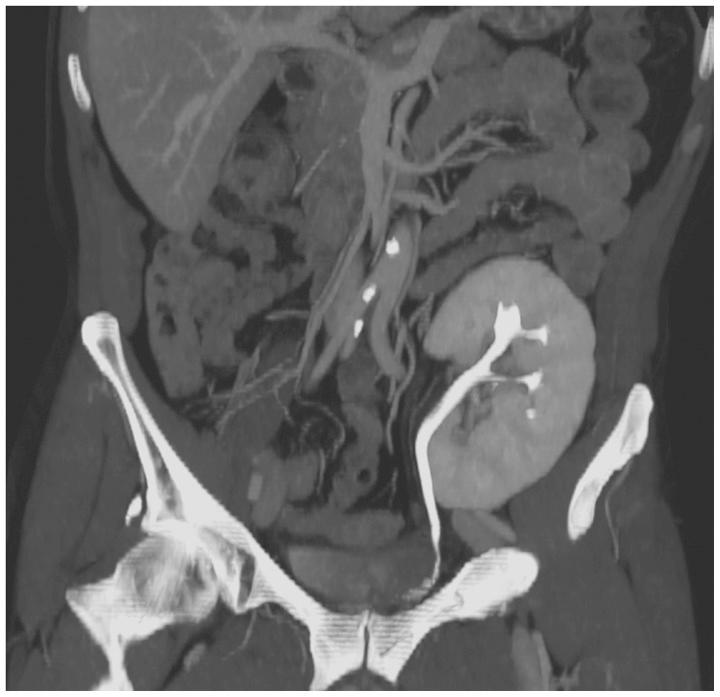

肾移植并发症的介入放射学治疗:图文综述

Interventional radiological treatment of renal transplant complications: a pictorial review.

Renal transplantation is the treatment of choice for patients with chronic renal failure, which produces a dramatic improvement in the quality of life and survival rates, in comparison to long-term dialysis. Nowadays, new imaging modalities allow early diagnosis of complications, and thanks to the recent developments of interventional techniques, surgery may be avoided in most cases. Knowledge in the types of renal transplant complications is fundamental for a correct pre-operative planning. In this article, we described the most common or clinically relevant renal transplant complications and explained their interventional management.

摘要

肾移植是慢性肾衰竭患者的首选治疗方法,与长期透析相比,它能显著提高生活质量和生存率。如今,新的成像方式可实现并发症的早期诊断,并且由于介入技术的最新发展,大多数情况下可避免手术。了解肾移植并发症的类型是正确进行术前规划的基础。在本文中,我们描述了最常见或临床上相关的肾移植并发症,并解释了它们的介入治疗方法。